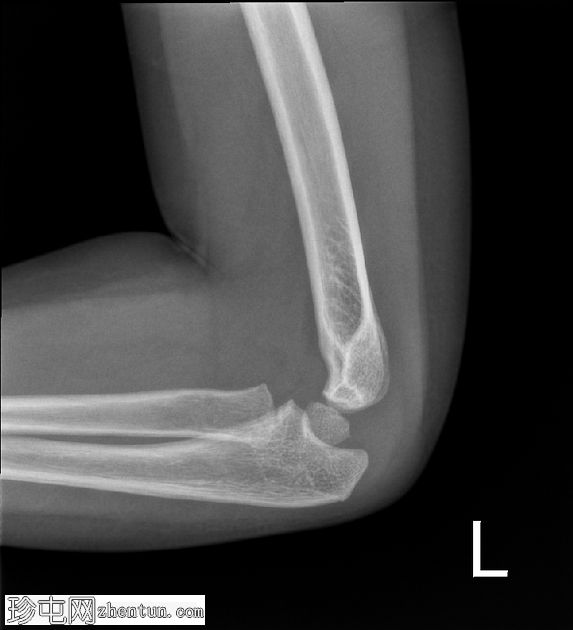

X光片

4.png

斜位

在正位片和侧位片上,桡骨近端干骺端可见轻微的皮质断裂和不规则,骨折线似乎向骺端延伸。

相关的脂肪垫征(可见前脂肪垫和帆状征,后脂肪垫阳性)进一步支持骨折后关节内积液的存在。

总体而言,骨性对线保持良好,无脱位迹象。

骨化中心与年龄相符。